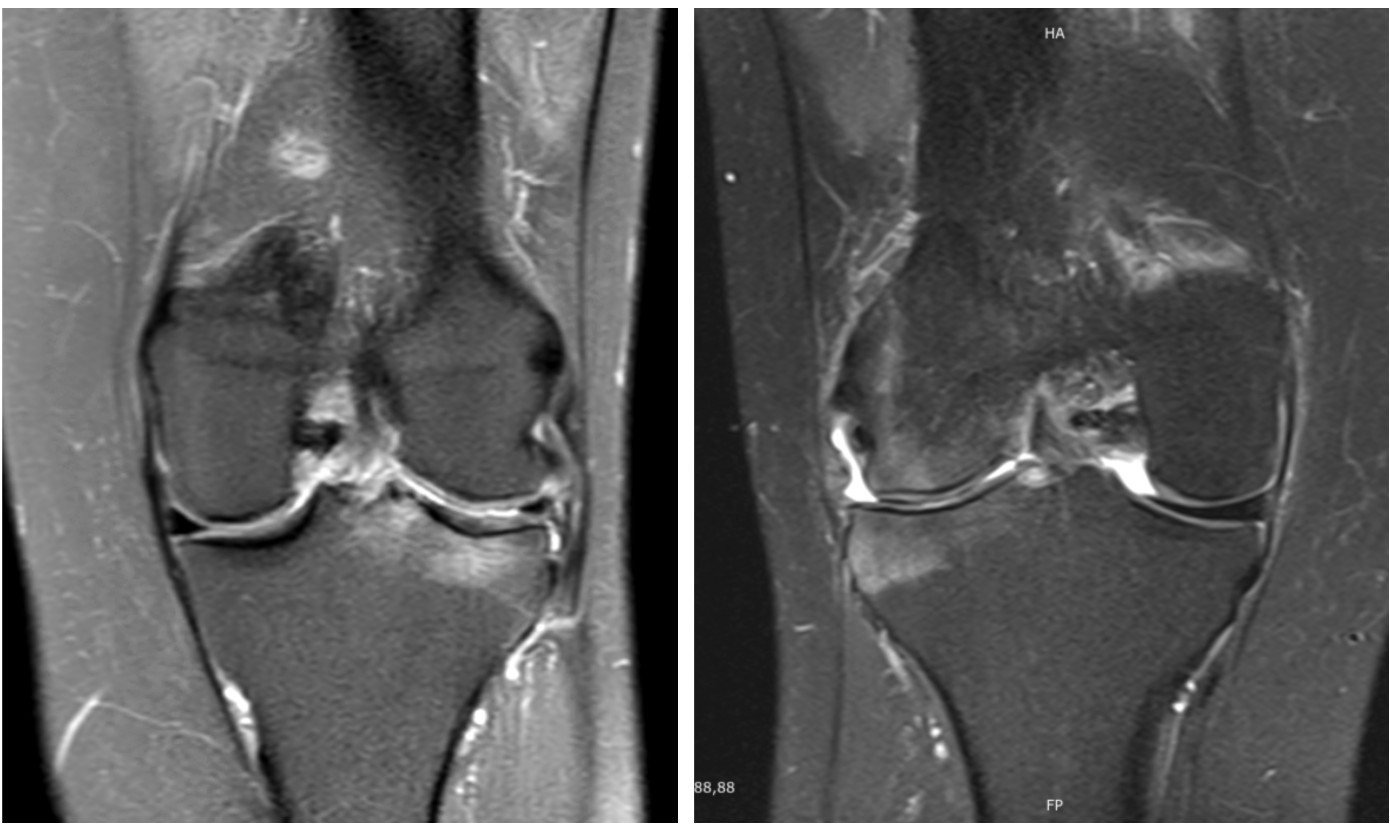

A subcondroplastia é um procedimento ortopédico desenvolvido para tratar lesões medulares ósseas (LMOs), também chamadas lesões do edema ósseo, frequentemente associadas a dores articulares crônicas e à progressão da osteoartrite. Essas lesões são caracterizadas por áreas de alterações microestruturais no osso subcondral, visíveis em exames de ressonância magnética (RM). Comumente, LMOs provocam dor significativa, redução funcional e podem acelerar o desgaste articular, levando à necessidade precoce de cirurgia de substituição articular.

- Lesões ósseas subcondrais sintomáticas identificadas em exames de ressonância magnética.

- Dor articular crônica associada a microfraturas subcondrais que não responderam satisfatoriamente ao tratamento conservador.

- Osteoartrite leve a moderada associada a lesões medulares ósseas.

Os locais mais comuns de aplicação incluem joelho (especialmente côndilos femorais e platô tibial), quadril e tornozelo. A técnica também é frequentemente indicada para pacientes que desejam postergar ou evitar procedimentos mais invasivos como a artroplastia total.